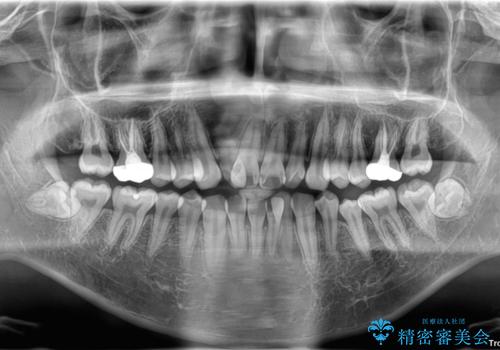

初診時の状態

・上下ともに歯がきれいに並びきらず、がたつきが見られました。

・上下の前歯の中心(正中)がずれています。

・特に上顎の幅が狭いため、下顎の歯列も内側に入り込み、歯が並ぶスペースが不足していました。

治療方針

このような歯列の狭さに起因するデコボコを改善するために、**MARPE(骨に固定する上顎急速拡大装置)**を使用して、上顎の横幅を拡大し、これにより歯が並ぶためのスペースを確保し、メタルブラケットを用いて歯列を整えていく計画としました。